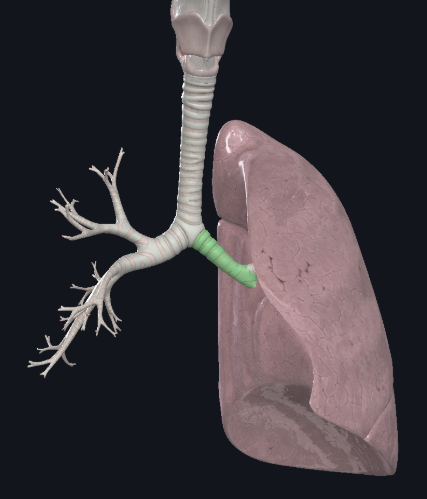

What structure is this?

Right main bronchus

What structure is this?

Right superior lobar bronchus

What structure is this?

Middle Lobar bronchus

What structure is this?

Right inferior lobar bronchus

What structure is this?

Left main bronchus

What structure is this?

Left superior lobar bronchus

What structure is this?

Left inferior lobar bronchus